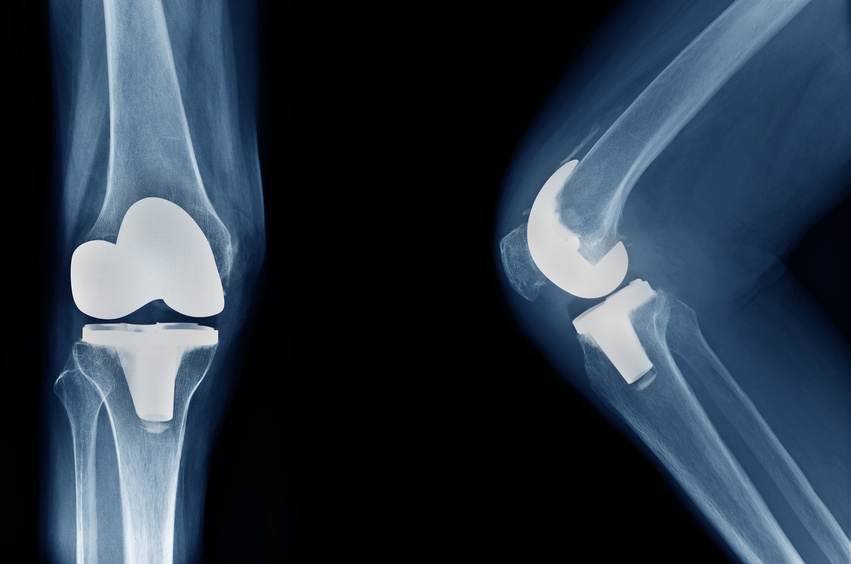

エビデンスに基づいた人工膝関節置換術後の理学療法

TKA後のROM・筋力・疼痛改善のポイント、歩行障害の原因やADLや復職,スポーツ復帰に対してエビデンスに基づいて学ぶセミナーです。